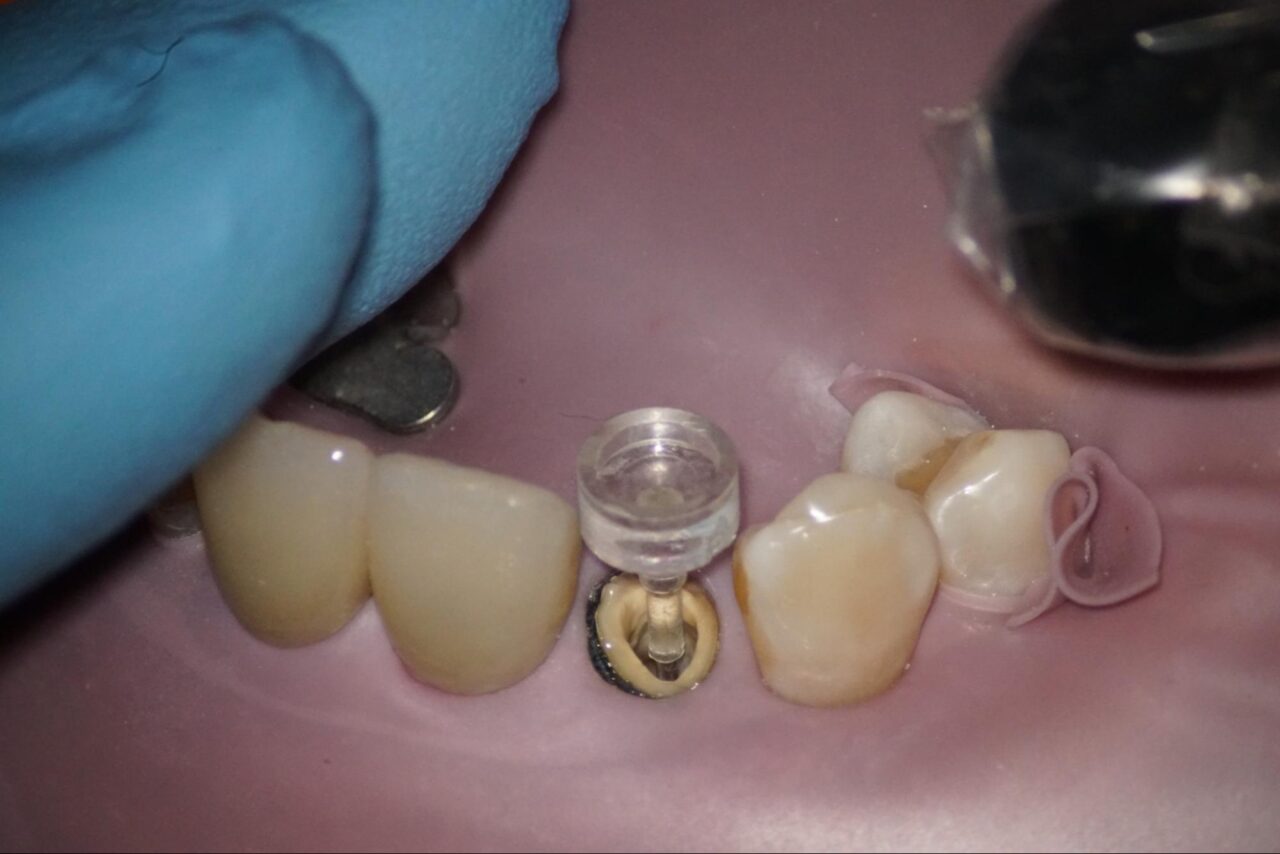

以前の根管充填材を取り除いて行きます。

以前の根管充填材は、感染部質なので完全に取り除く必要があります。この写真では根尖部にまだ残っている事が確認できます。

根管内、根尖部がきれいになったと思われるので、根管洗浄を6%次亜塩素酸を満たした状態で根管内にレザーを用いて活性化させて細かいとことまで洗浄を行います。

根管内がきれいになっている事が、確認できます。

バイオセラミックによる根管充填を行いました。